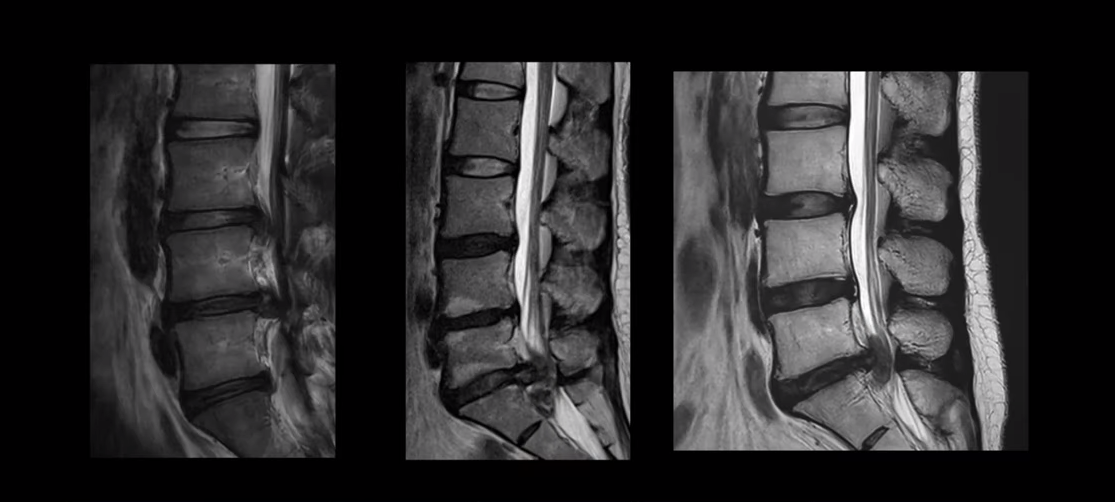

여기 MRI를 보시면 디스크 파열이 엄청나게 심한 분들입니다. 보시다시피 파열이 너무 심해서 이런 분들이 정형외과나 신경외과 가시면 거의 다 바로 수술하라는 얘기를 듣습니다. 그런데 이런 심한 파열일수록 오히려 치료가 더 잘 될 가능성이 매우 높다고 말씀 드리는 겁니다. 이분들 비수술 치료후기는 아래 영상을 참고하시길 바랍니다.